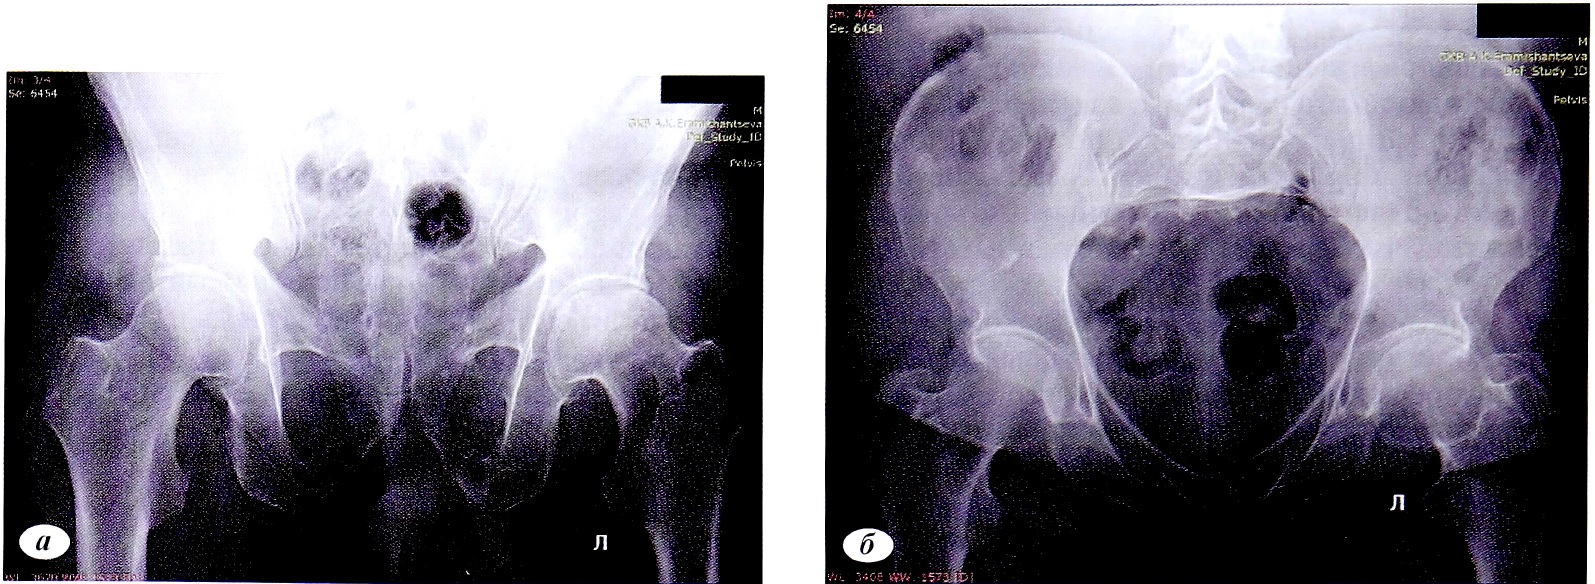

Клинический пример 1. Пациентка Р.,68 лет, травма в результате ДТП, пассажир. Доставлена бригадой скорой медицинской помощи (СМП). Установлен диагноз: политравма. Перелом боковых масс крестца справа Denis I. Перелом седалищной кости справа со смещением отломков. АО/ОТА — 61 -В2.1 Перелом поперечных отростков слева L3—L5 (рис. 1). Закрытый перелом дистального метаэпифиза обеих костей правого предплечья со смещением отломков. Ушиб грудной клетки. По шкале ISS 21 балл.

Рис. 1. Пациентка А,68 лет. Компьютерная томограмма,3D-реконструкция, визуализирован перелом поперечных отростков слева L3-L5. Перелом боковых масс крестца слева Denis I.

Fig. 1. Computed tomogram,3D reconstruction, visualized fracture of the transverse processes on the left L3—L5. Fracture of the lateral masses of the sacrum on the left Denis I.

После стабилизации состояния пациентки была предпринята попытка активизации. В связи с наличием ипсилатерального перелома верхней конечности и выраженного болевого синдрома в пояснично- крестцовой области на 3-и сутки одномоментно была выполнена фиксация крестца справа канюлированным винтом 7,0 мм. Остеосинтез костей предплечья был осуществлен пластинами и винтами. Пациентка была активизирована на 1-е сутки после операции. Послеоперационный период без осложнений.

Отдаленные результаты через 12 мес: на контрольных рентгенограммах определялись консолидированные переломы боковых масс крестца справа, седалищной кости справа (рис. 2). По шкале S. Majeed — 85 баллов, по тесту «Timed up & go» [30] 9 с (рис. 3).

Рис. 2. Пациентка, Р. 68 лет. Рентгенография консолидированного перелома боковой массы крестца справа через 12 мес после операции. Остеосинтез канюлированным винтом. Консолидированный перелом седалищной кости справа, а — проекция: выход из таза; б — проекция: вход в таз.

Fig. 2. Radiography of a consolidated fracture of the lateral sacrum mass on the right, one year after surgery. Osteosynthesis by cannulated screw. Consolidated fracture of the ischium on the right, a — outlet view; 6 — inlet view.